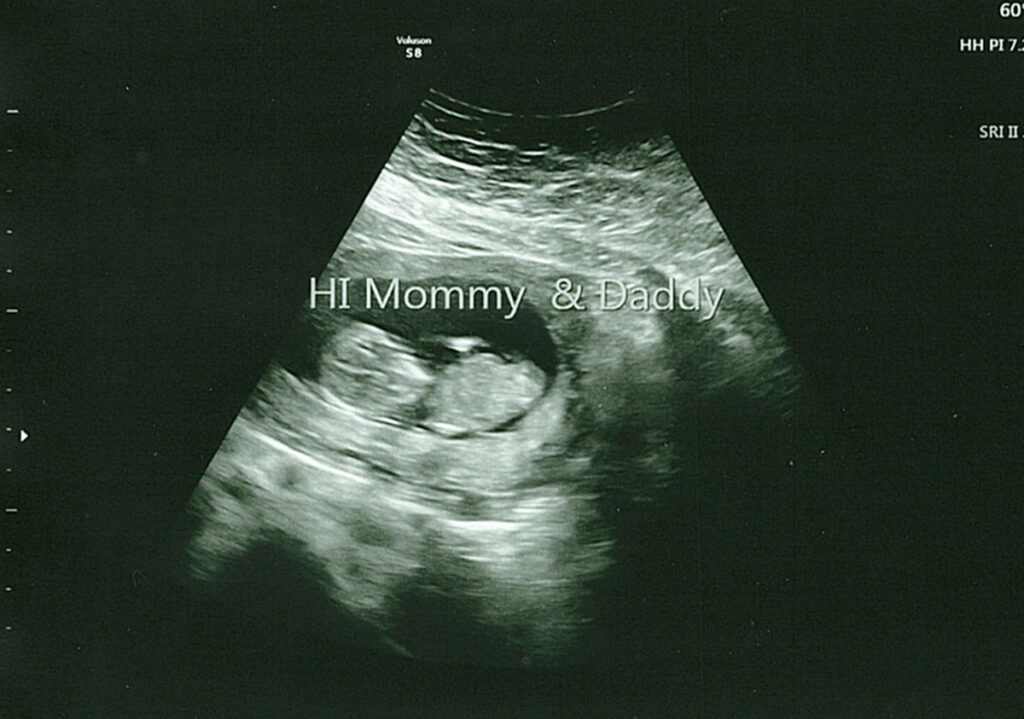

I’m happy to report the visit went amazing, and we couldn’t have asked for a better ultrasound tech. She first let us hear the heartbeat and even spent extra time with us, trying to get better photos (though I need to drink more water). She let us record the visit, and I’ve included a few pictures and a short video clip showing our baby moving around. Life is such a miracle, and seeing this baby, the size of a lime, move around was incredible.

This pregnancy – Video Clip from Our 12 Week Ultrasound

Here’s a short clip from our visit where you can see our baby moving around. This visit was exactly what we needed, and I feel even more connected to this little human, though it’s still crazy to think they’re growing inside my body.